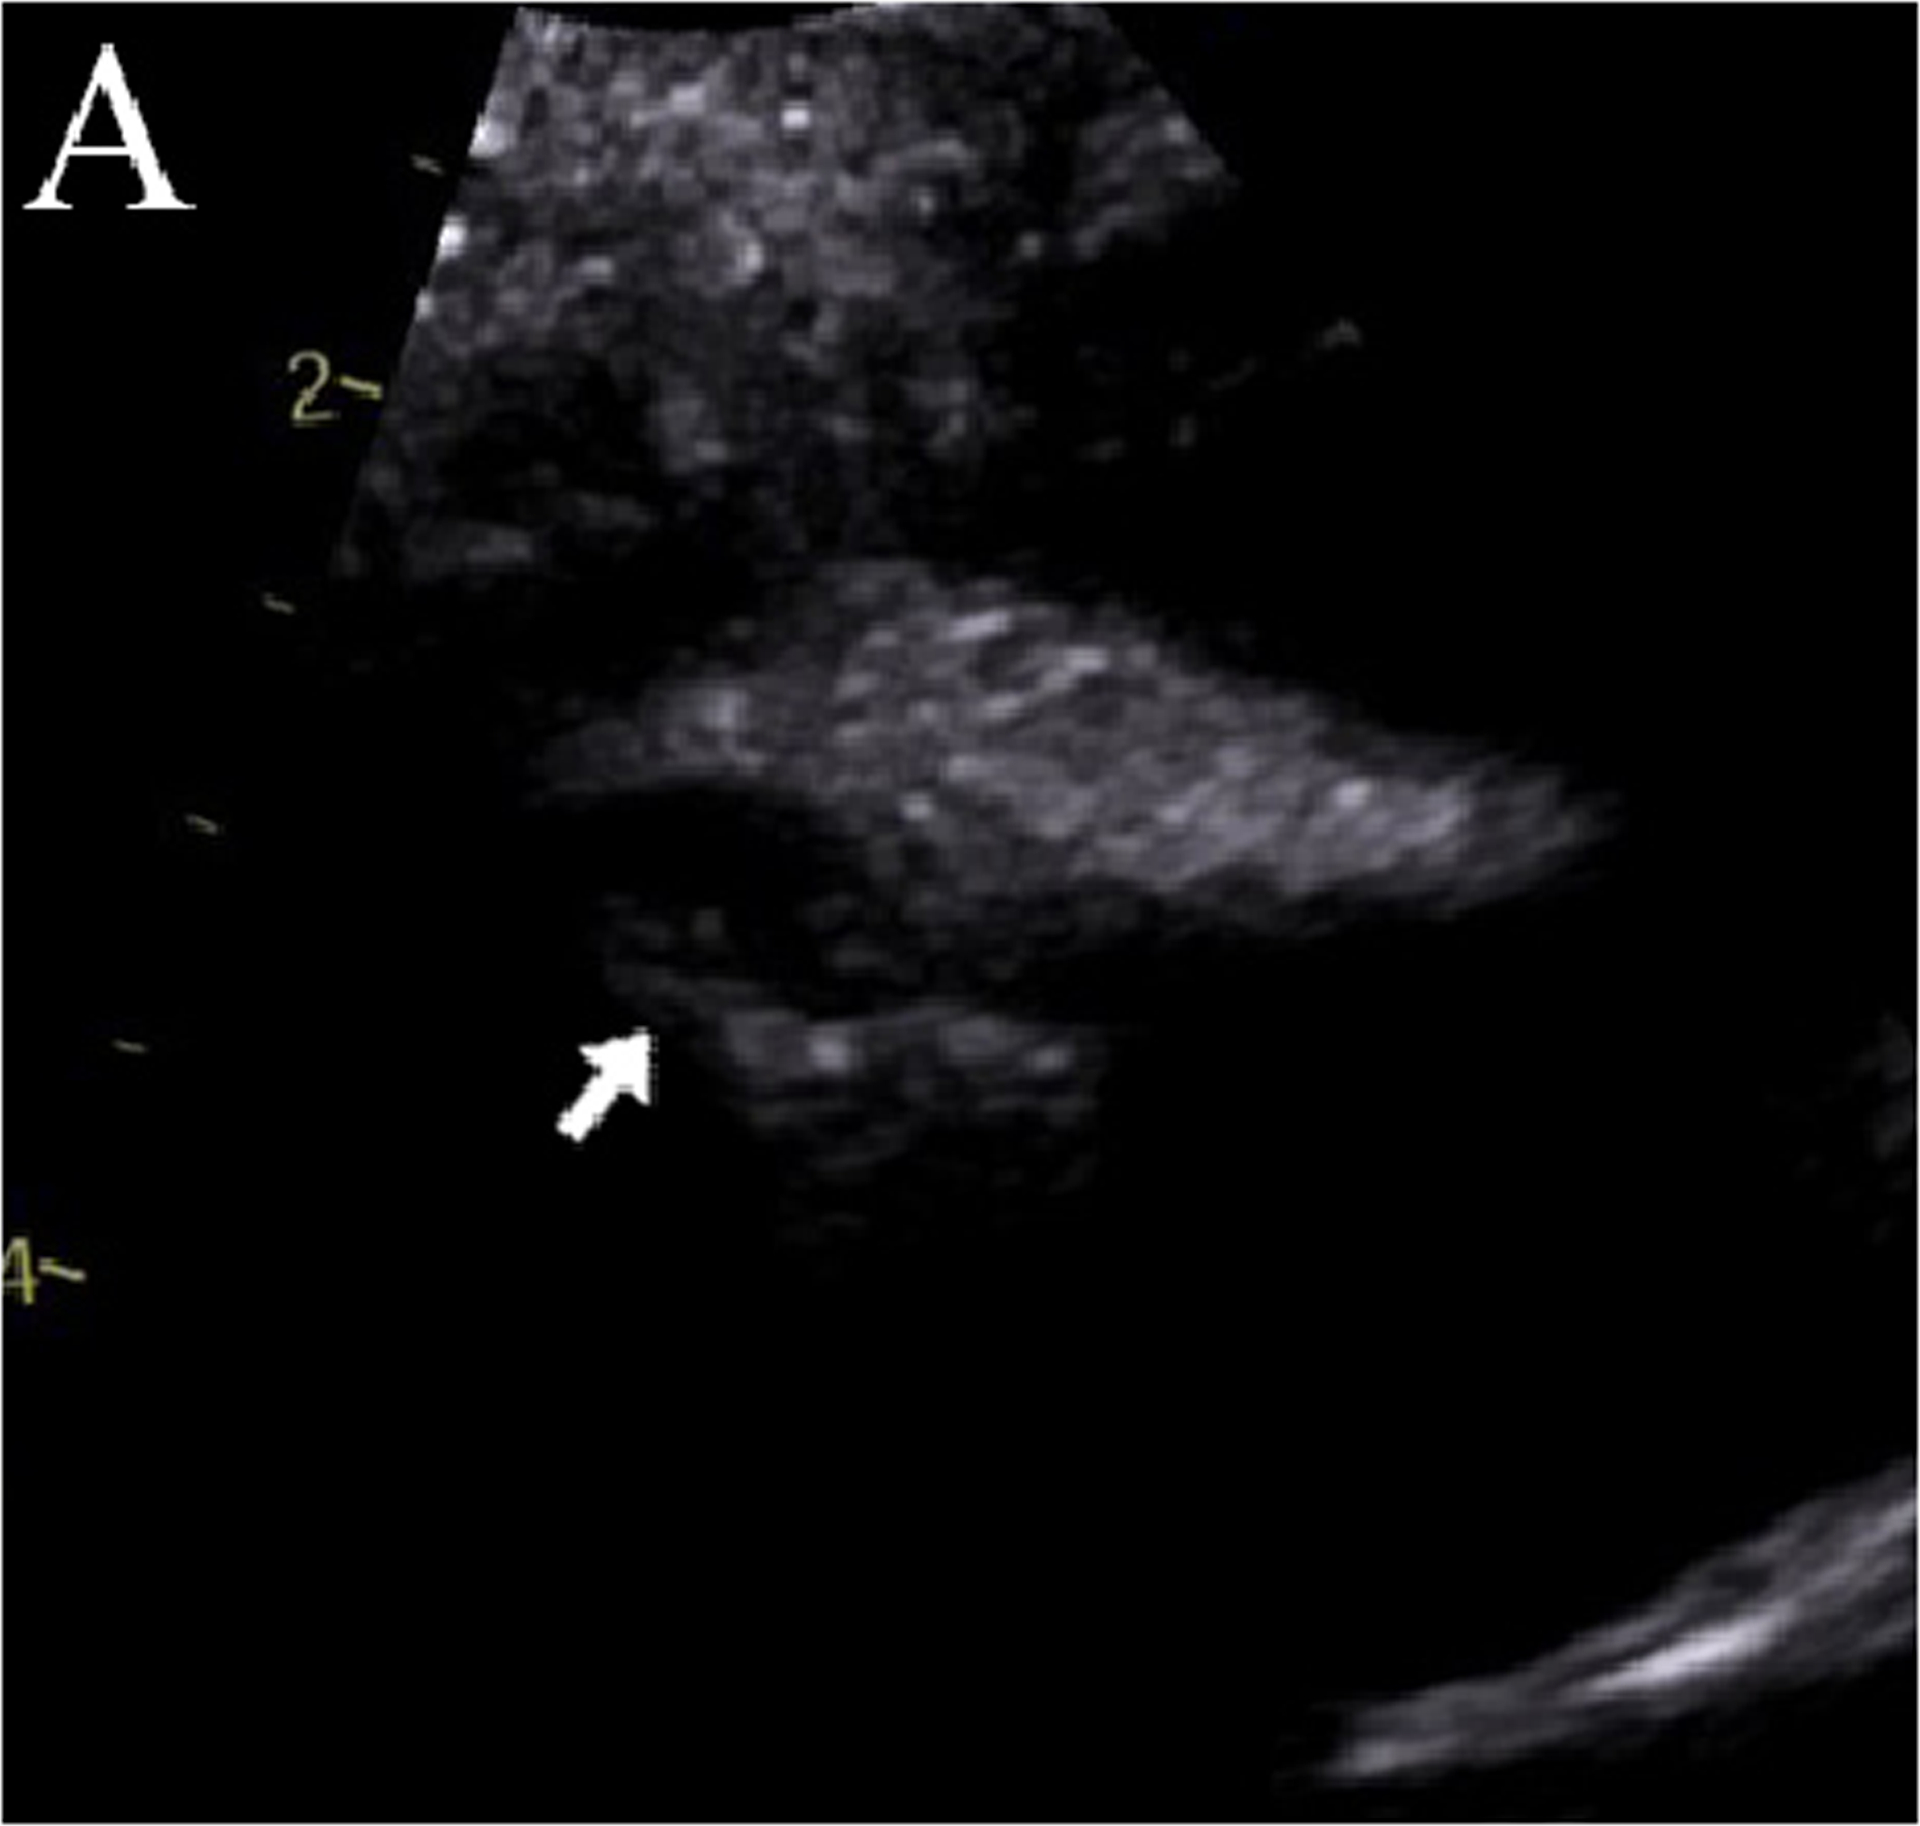

A 5-year-old boy had onset of MIS-C symptoms 55 days after COVID-19 illness and 15 days after receiving his first BNT162b2 COVID-19 vaccination. He was admitted three times for MIS-C, twice after his steroid dose was tapered. On his initial admission, he was given intravenous immunoglobulin (IVIG) and steroids. During his second admission, new, moderate coronary dilation was noted, and he was treated with IVIG and steroids. At his last admission, worsening coronary dilation was noted, and he was treated with infliximab and steroids. During follow-up, he had improvement in his coronary artery dilatation. However, his inflammatory markers increased after steroid wean, and his steroid taper was further extended, after which time his inflammatory markers improved. This is the only such reported case of a patient who was admitted three times for MIS-C complications after Covid-19 vaccination.